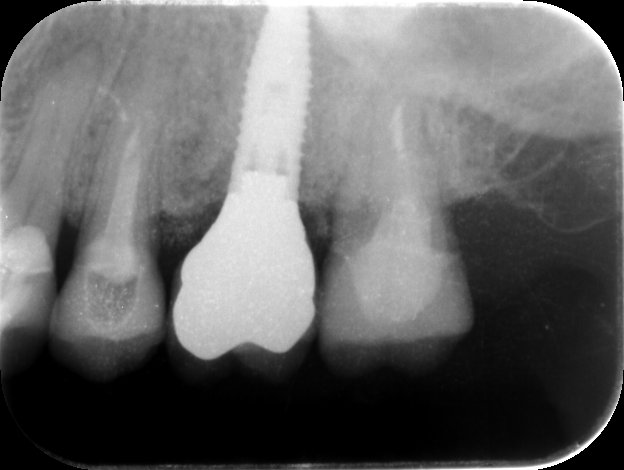

2019年10月21日 624 × 470 歯が折れて抜かないといけないのですが、その後入れるものをブリッジかインプラントかで悩んでいます。前後の歯は問題ないと言われましたが、どうでしょうか?

1歯症例の補綴症例(インプラント)